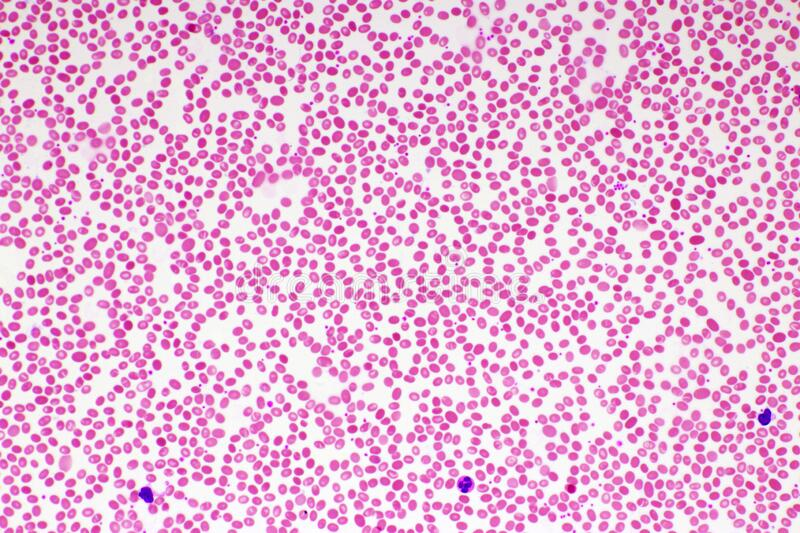

* 10. ¿Qué tipo de células ves en la fotografía de microscopía? Pista: en el libro dice que son estrelladas, pero en verdad son alargadas.